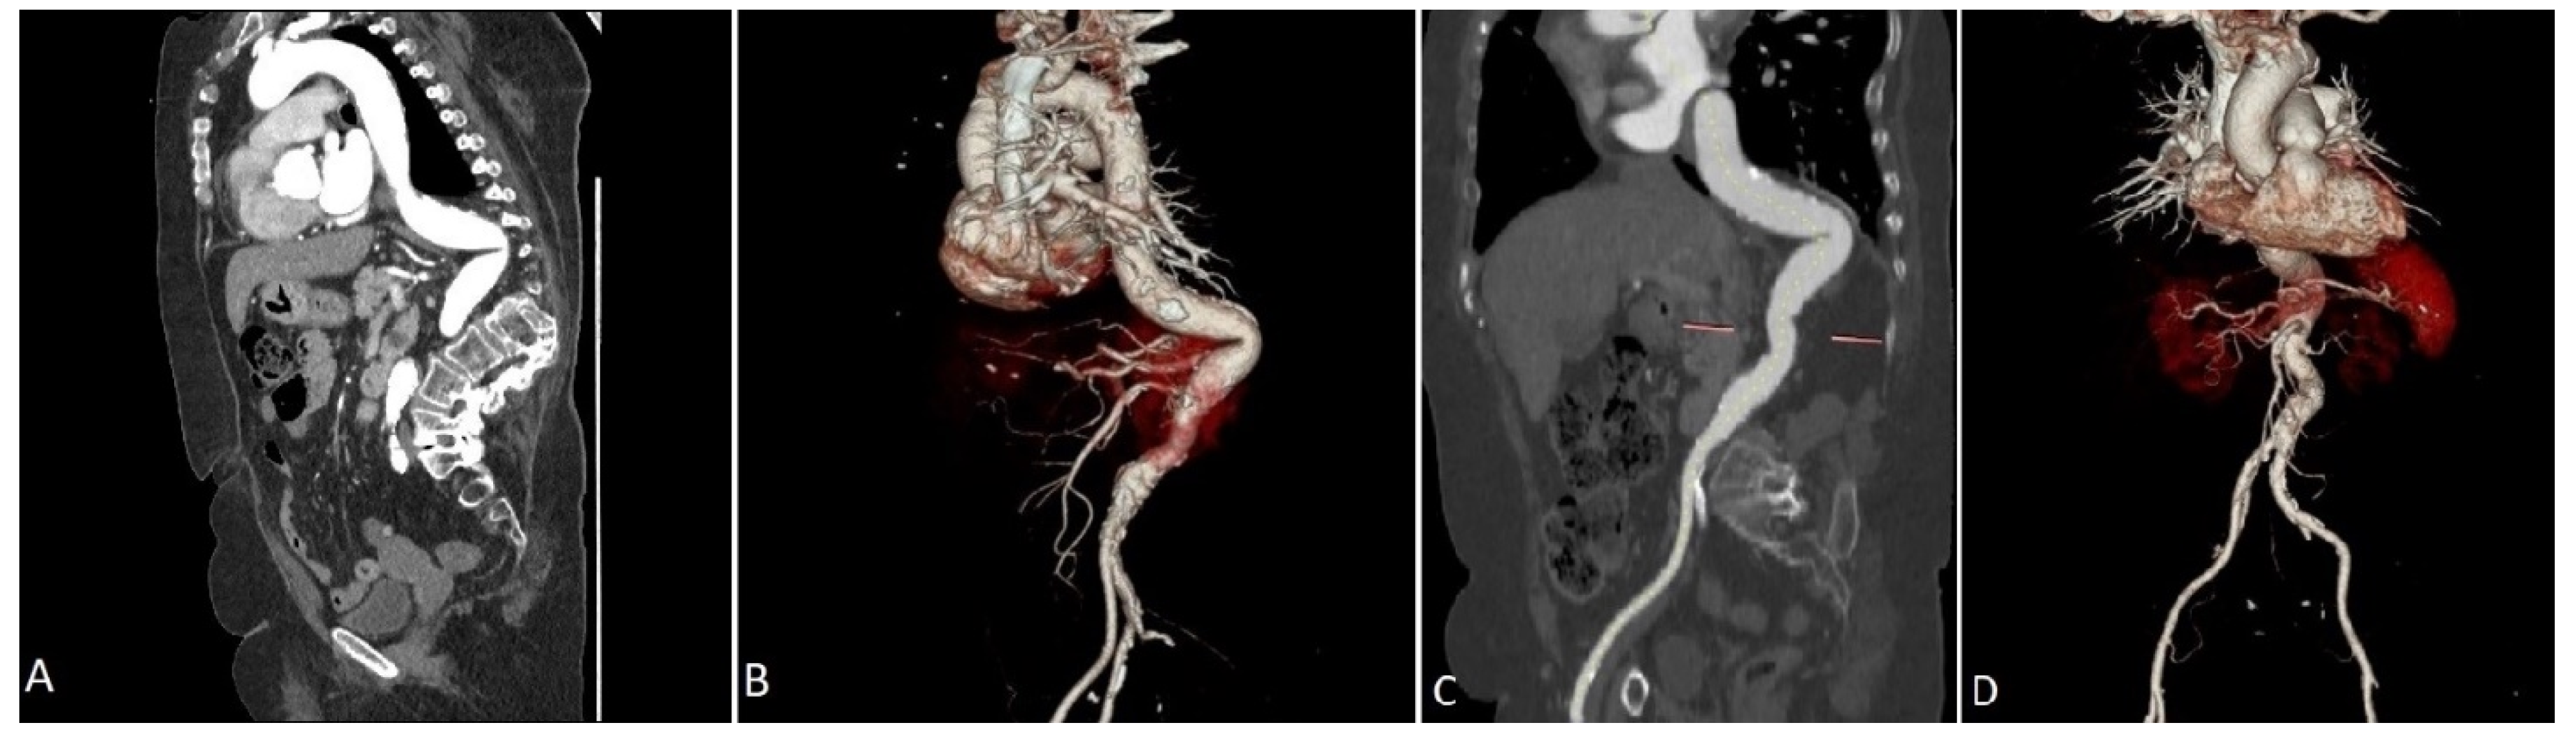

2. Case Presentation